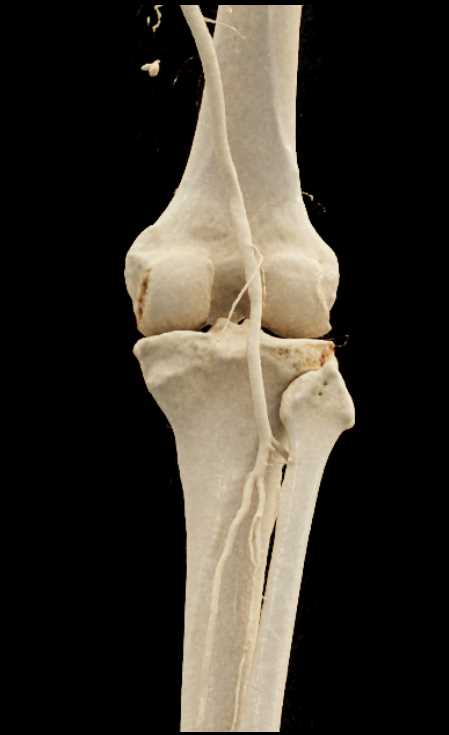

GSW with Bleed Near Knee